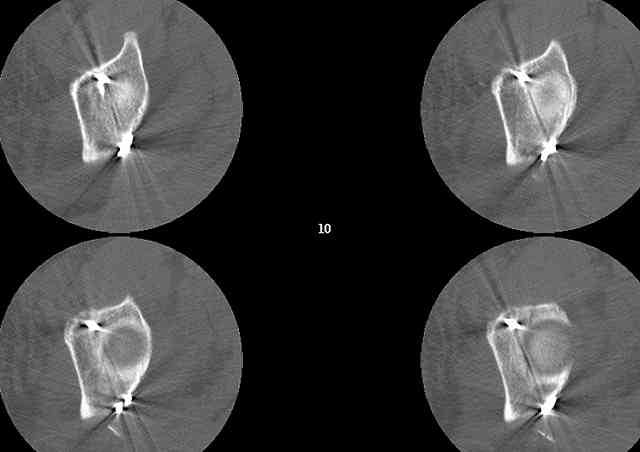

A CT scan will rarely lie to you...reveals your reduction and implants...we use it to assess, teach, grade, and try to get better next time.

Screw Fixation

-AC Screw

-PC Screw

For Alex... here are some cannulated and 7mm screws for you... notice the fracture malreduction as indicated by the head subluxation on both views...this was a percutaneous technique without open reduction... I don¹t like it but there it is... the fixation technique is not at fault, because there was no open reduction of the fracture... but let¹s not get in to all that.